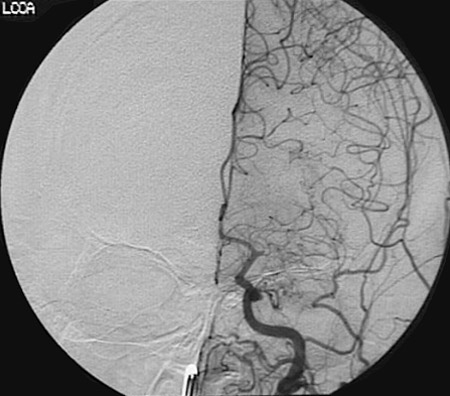

This angiogram demonstrates an embolic obstruction of the initial (horizontal) segment of the middle cerebral artery.